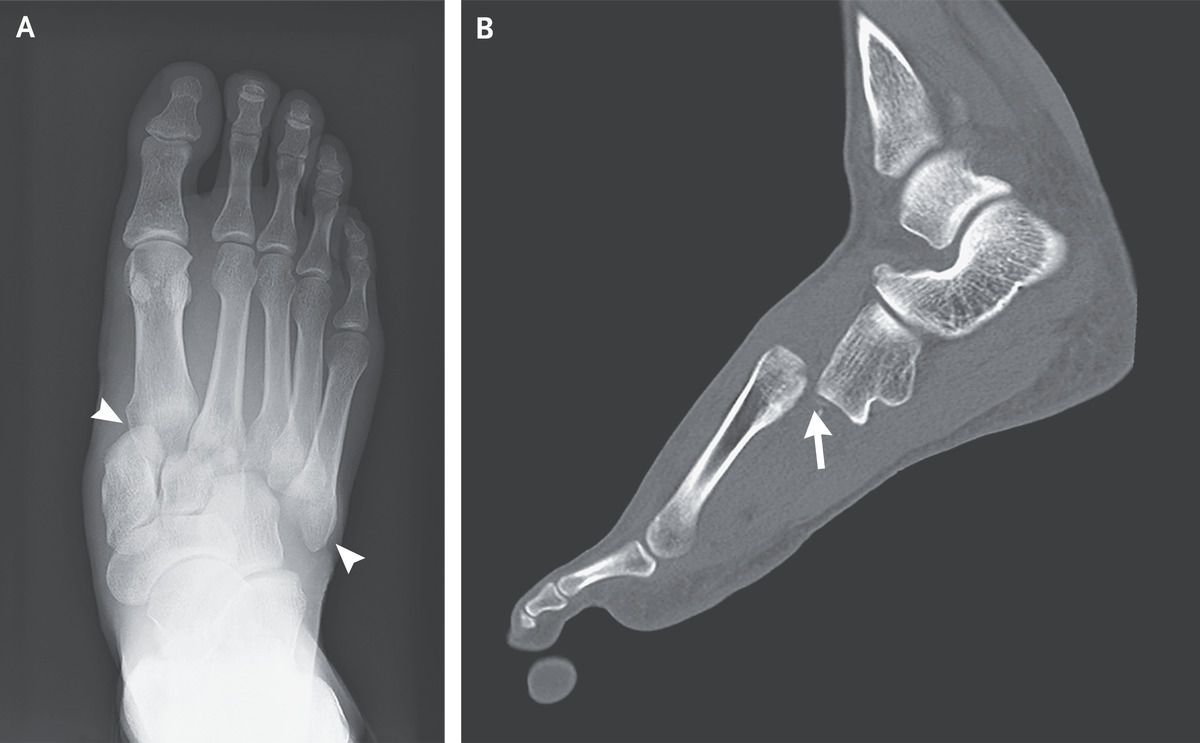

A 34-year-old man presented to the emergency department with sudden onset of pain in his right foot after landing a jump during a handball game. On physical examination, there was swelling and bruising on the dorsum of the right foot, and the patient was unable to bear weight on the foot. Non–weight-bearing radiographs showed lateral displacement of the first through fifth metatarsal bones from the cuneiform bones and the cuboid (Panel A, arrowheads). Computed tomography of the right foot revealed lateral and dorsal dislocation of the first through fifth metatarsal bones from the cuneiforms and cuboid (Panel B, arrow), as well as fractures of the first and second proximal metatarsals. The patient received a diagnosis of Lisfranc injury — an injury to the tarsometatarsal joint complex that can range in severity from soft-tissue damage to fractures with displacement. Lisfranc injuries are rare and may be misdiagnosed owing to subtle findings on radiography or to the presence of other, distracting injuries. The presence of substantial foot pain after even minor trauma should arouse suspicion for this condition. The patient underwent immediate surgical repair without complications. At follow-up 10 weeks after surgery, he could fully bear weight on the foot, and at follow-up 6 months later, his gait was normal. Hiroyuki Funatomi, M.D. Akira Kuriyama, M.D., M.P.H., Ph.D. Kurashiki Central Hospital, Okayama, Japan